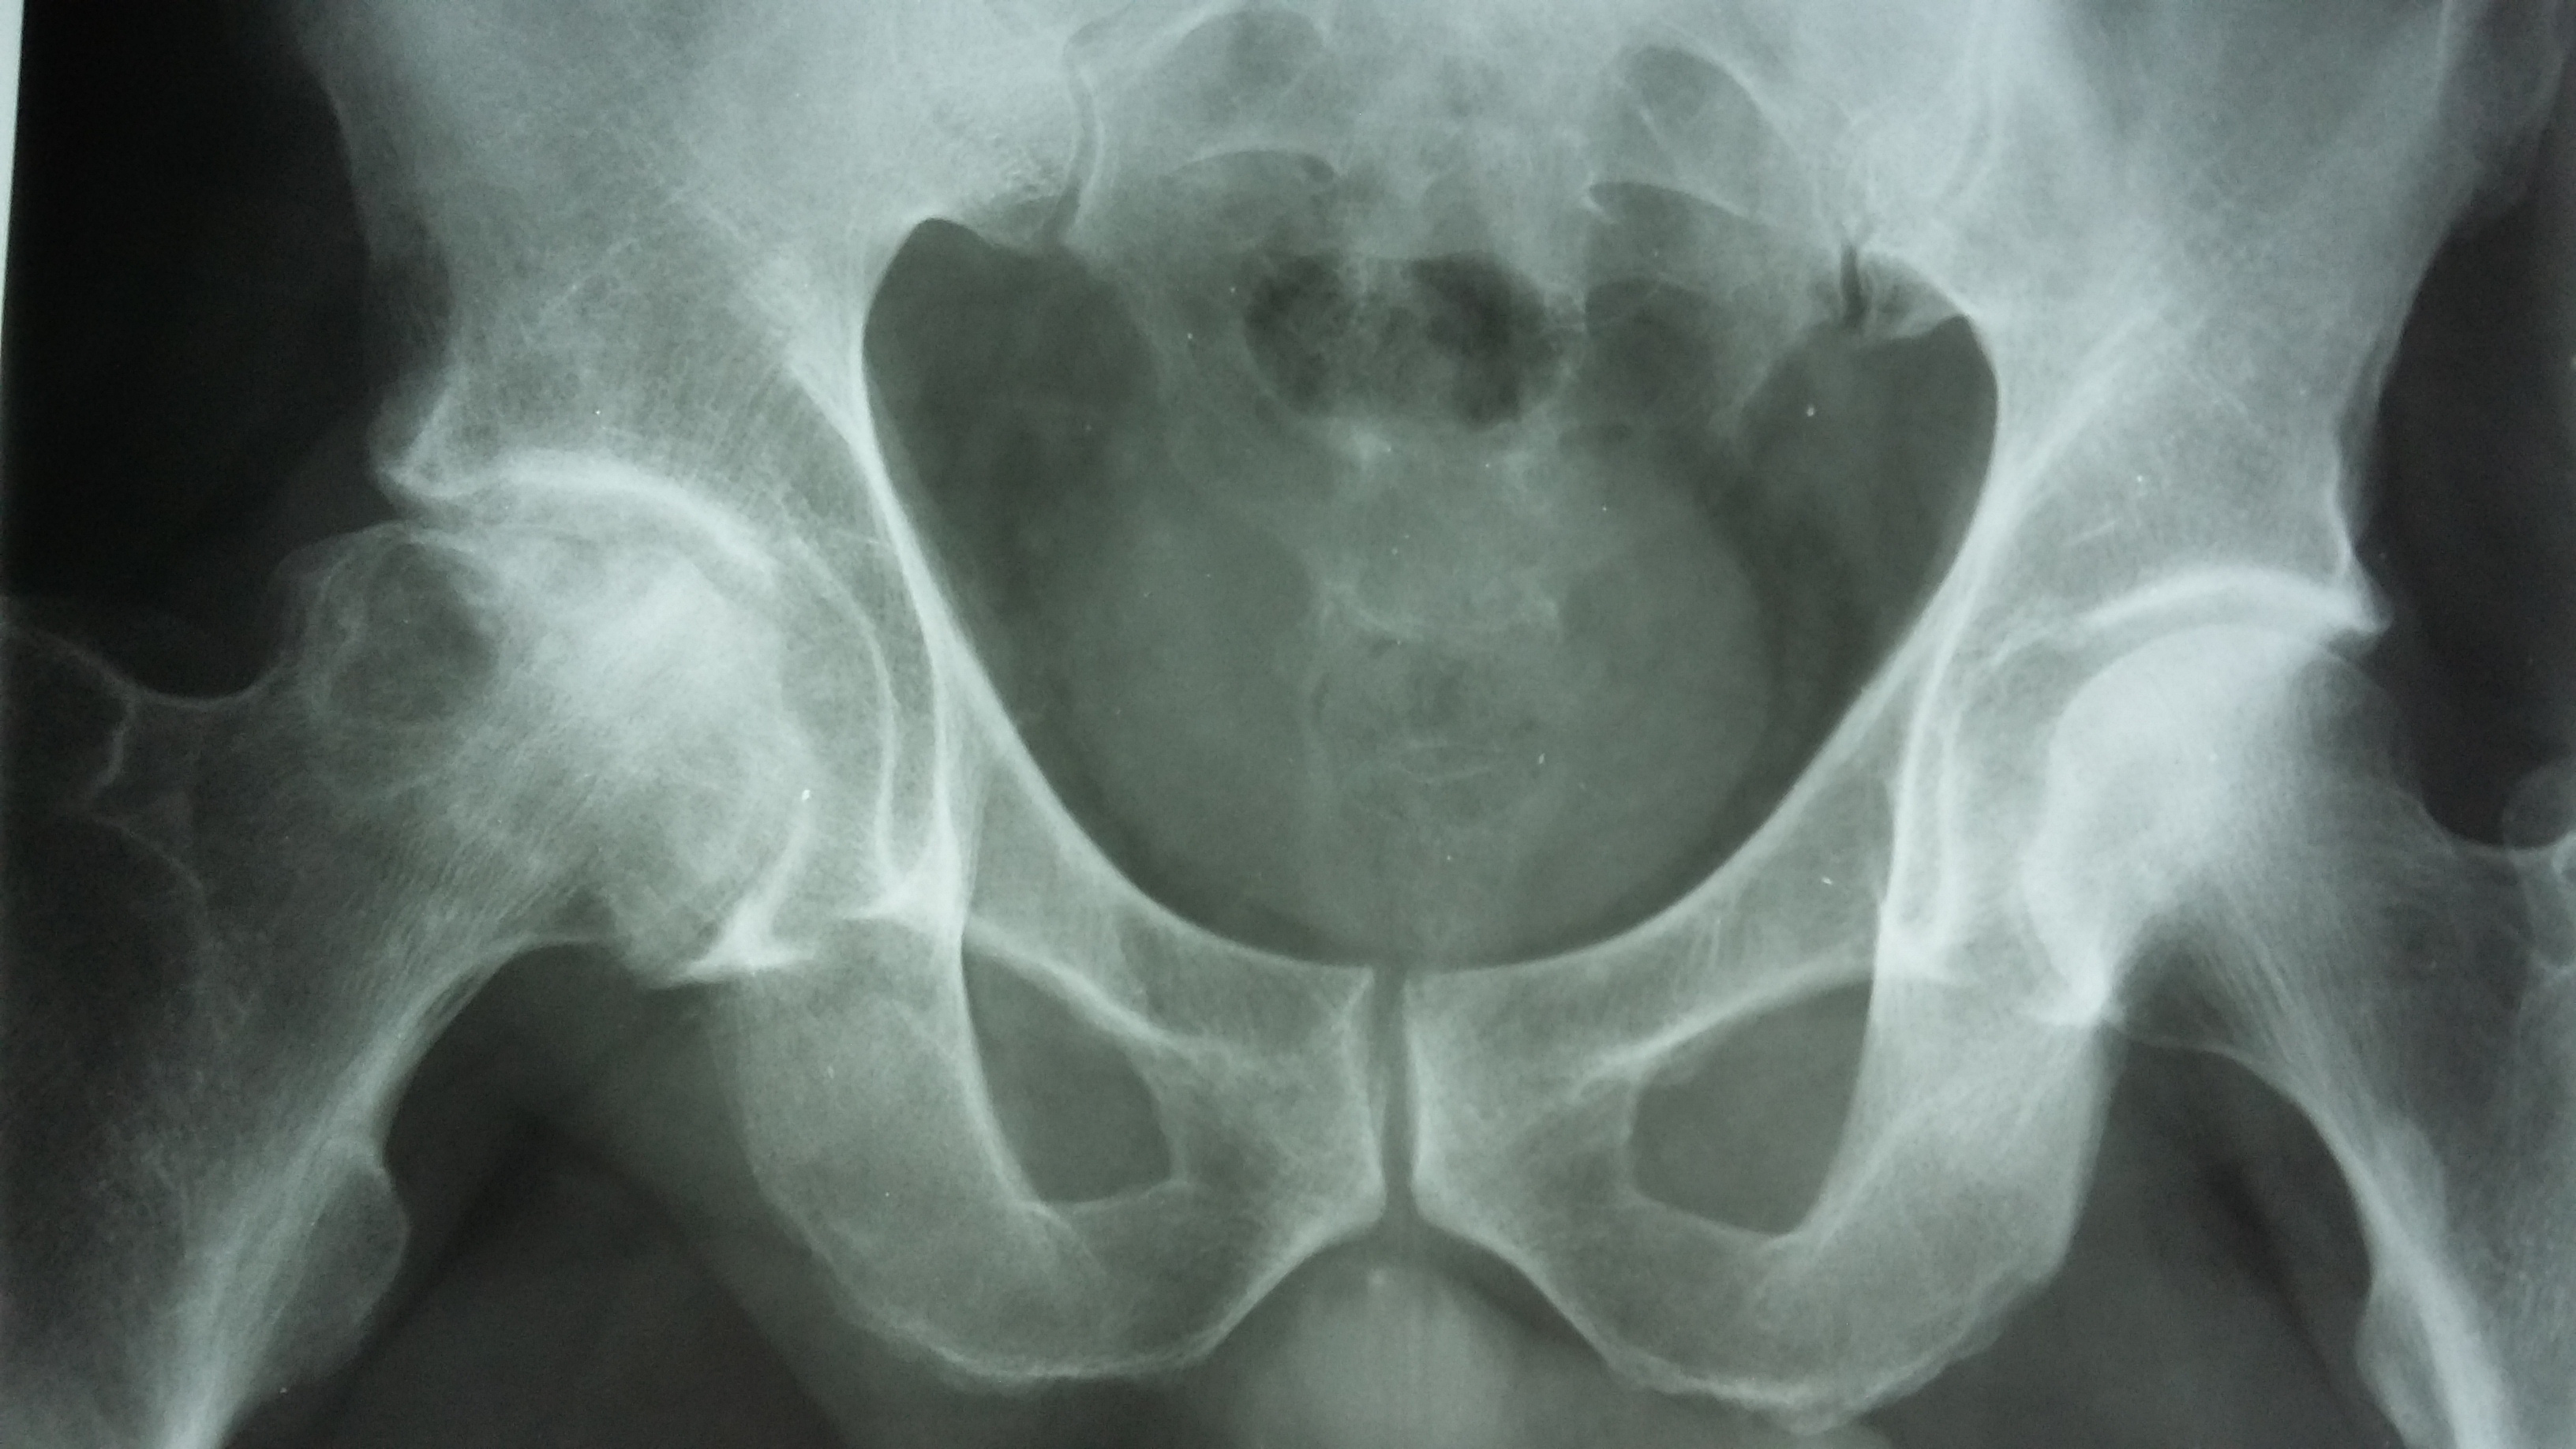

Диагностика ТБС рентгеном и асептический некроз: особенности лечения

Раздел: Снимки-откровения